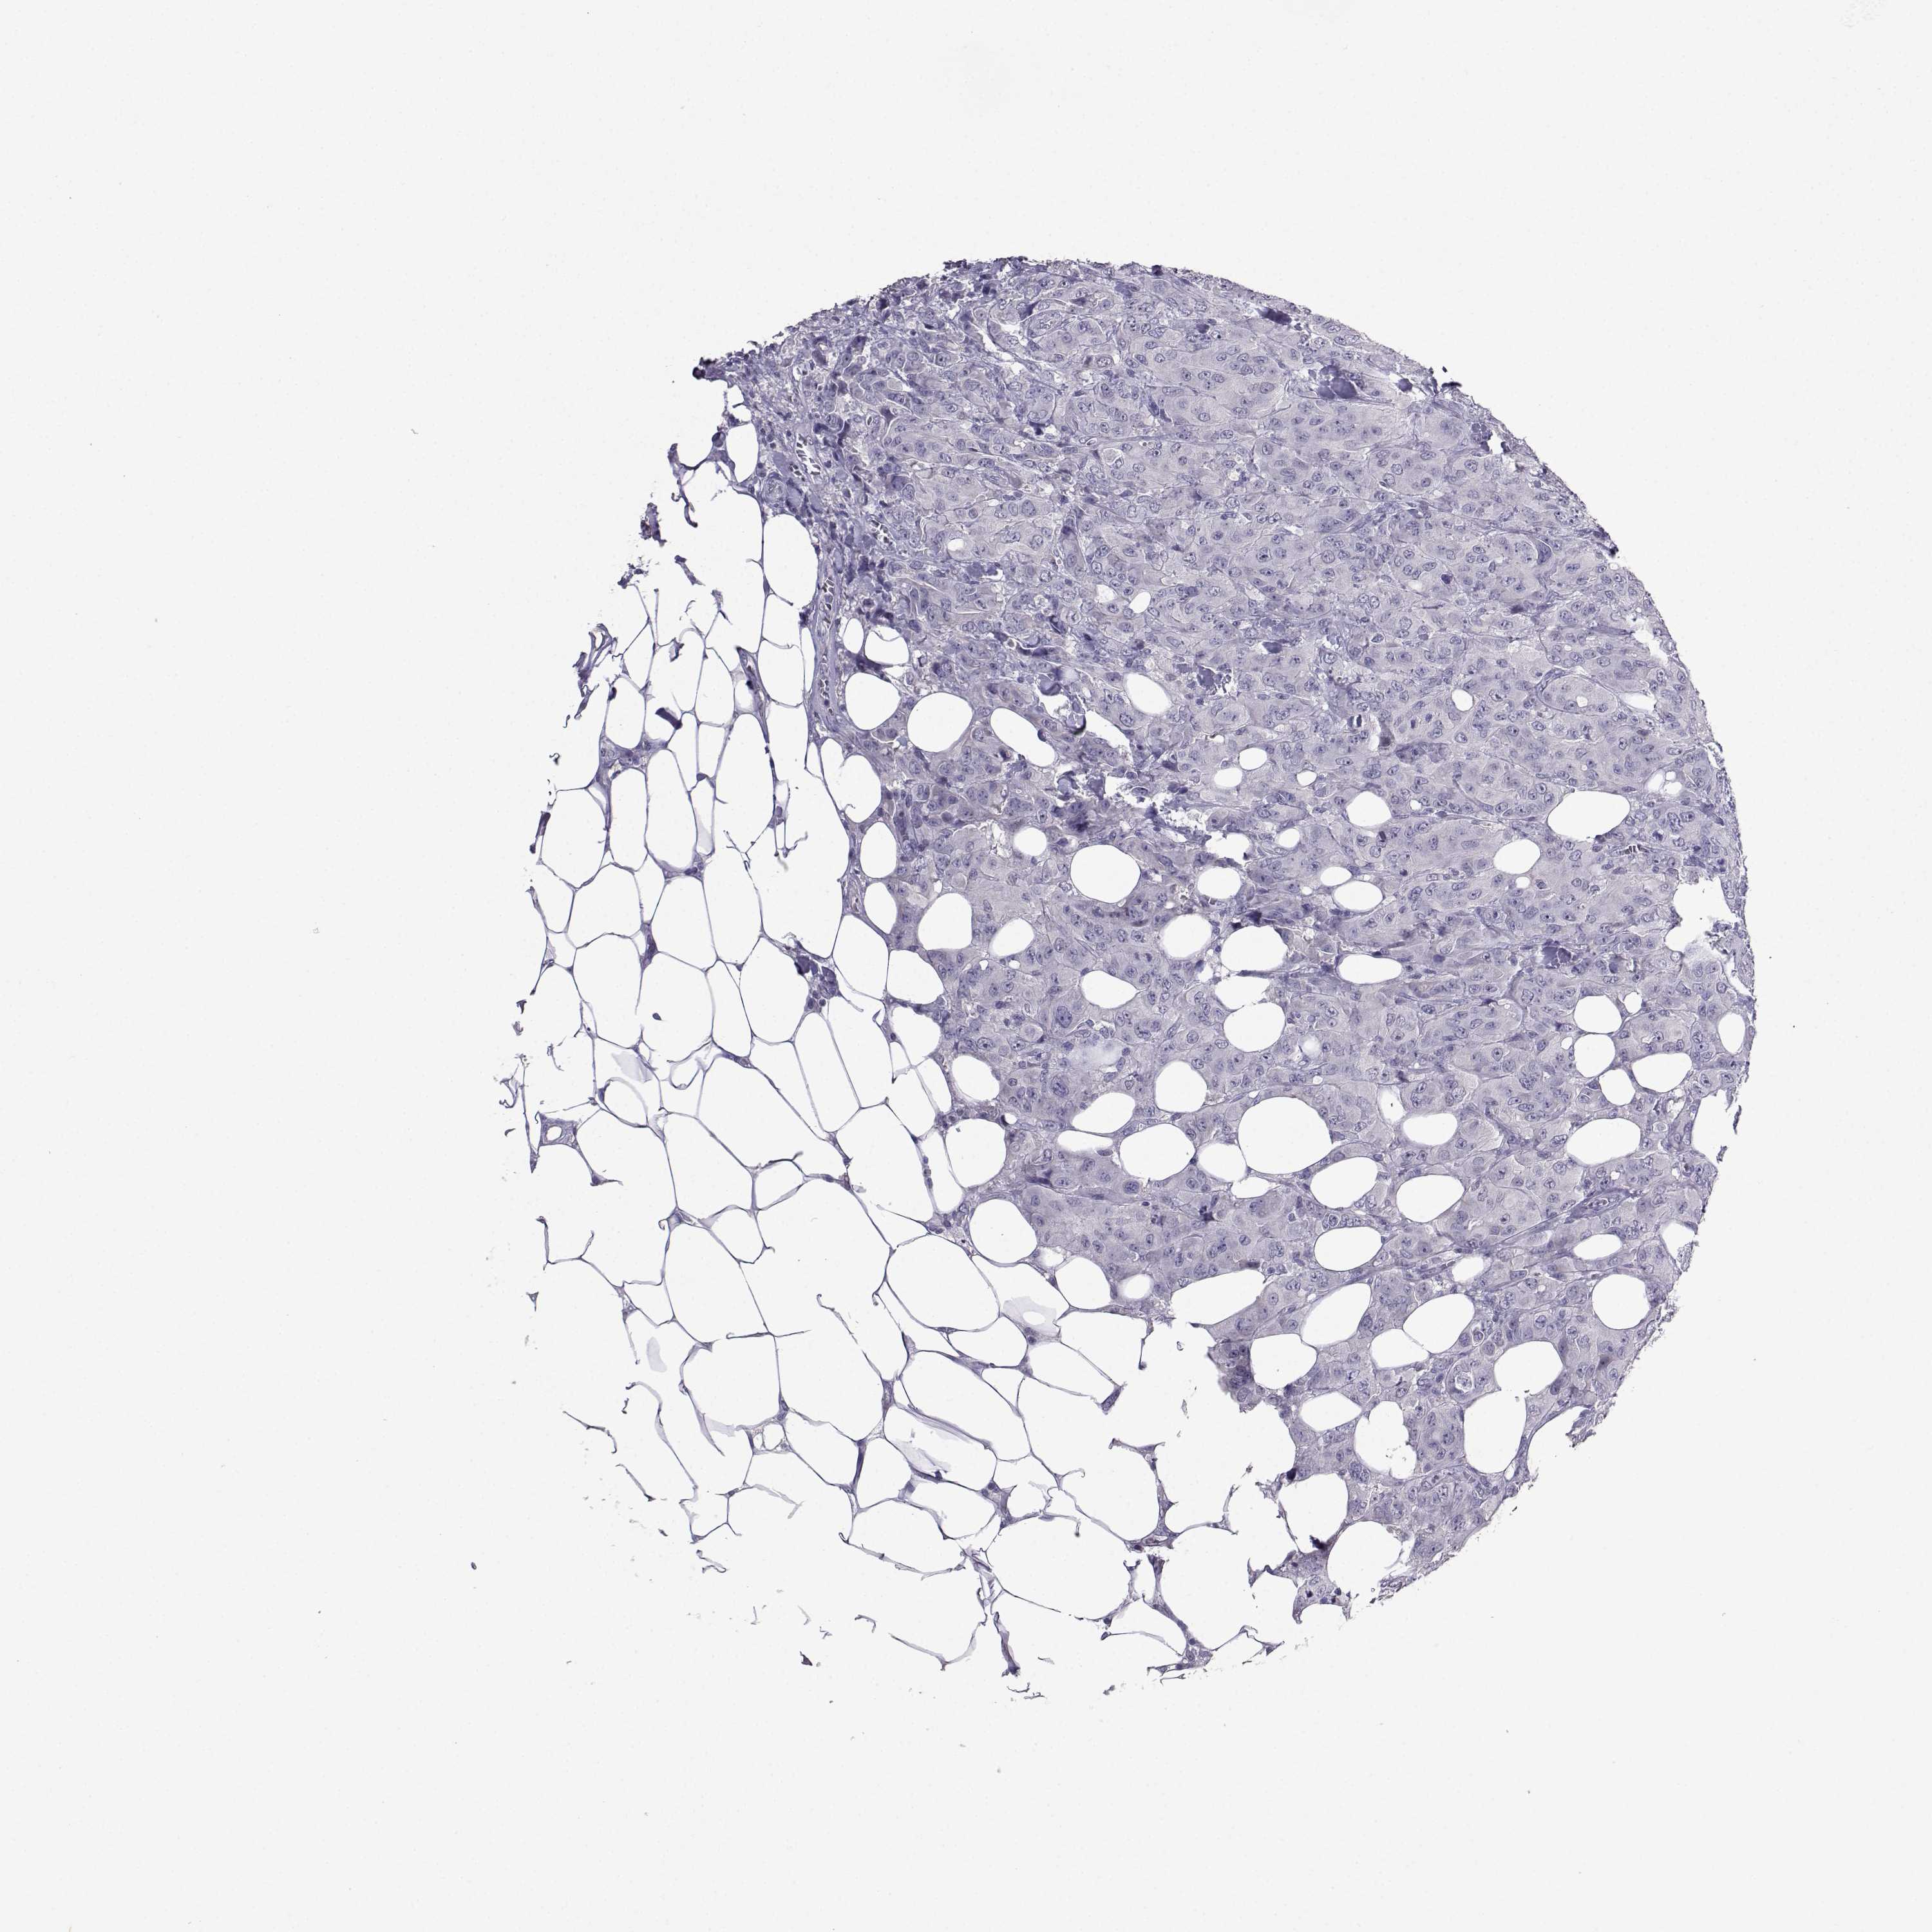

CANCER BREAST CANCER Show tissue menu

BRCA TCGA BRCA VALIDATION PROTEIN EXPRESSION